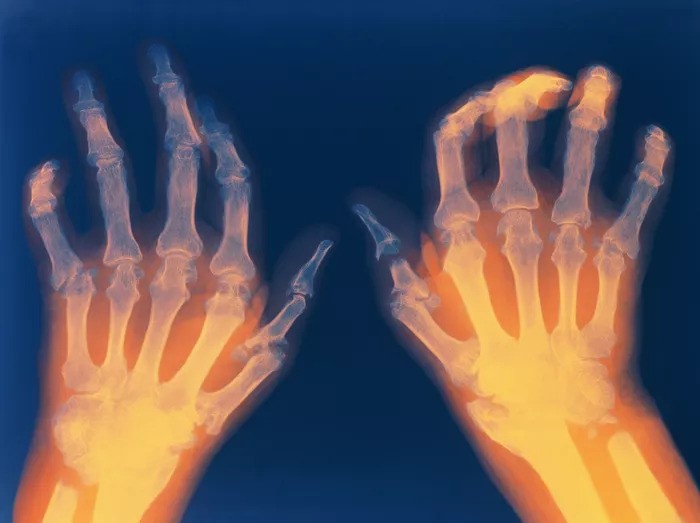

Viêm khớp dạng thấp là tình trạng viêm đặc hiệu xảy ra ở các khớp gây tổn thương màng hoạt dịch, sụn khớp và đầu xương dưới sụn, diễn biến mạn tính dẫn đến tình trạng dính và biến dạng khớp.

Viêm khớp dạng thấp là tình trạng viêm đặc niệu xảy ra ở các khớp gây tổn thương màng hoạt dịch

Khi hệ thống miễn dịch bị tấn công, lớp màng hoạt dịch synovium bao quanh khớp bị viêm và dày lên, cuối cùng dẫn tới việc phá hủy sụn và xương trong khớp. Thêm vào đó các gân và dây chằng giữ các khớp với nhau cũng bị giãn và suy yếu khiến cho khớp bị biến dạng và mất tính liên kết.